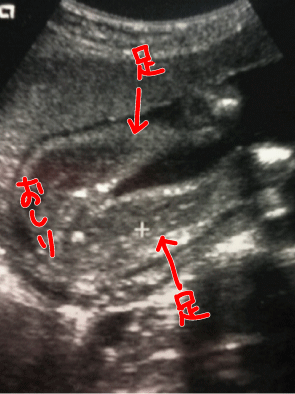

昨日、7月11日(日)は妊婦検診やった。

ずっと気になっていた

3人目の性別。

私 : 先生、性別がわかったら教えてください。

先生 : もちろん、わかったら言うよ。一緒にみよう!

早速検査が始まった。

目を凝らしてお股を確認するけれど

男の子に見えない。

私 : 先生、コレ何にもついてないですか?

先生 : うーーん。多分、これが子宮だと思うんだけど

まだ小さいから何とも言えないなぁ。

私 : えっ。ほんなら女の子の割合の方が高いんですか?

先生 : うーーん。そうだねーー。

次は2週間後です。子宮が見えれば女の子確定かなぁーー。

エコー写真の達人の方がいらしたら、どっちか教えてください(笑)

うちは、2人とも生まれるまで「たぶん女の子だと思います」と言われて、確定はしてもらえませんでした。けえこさんのエコー写真を見る限り、うちの子よりもはっきりとお股が見えているので女の子確率は80%くらいですかね?(笑)